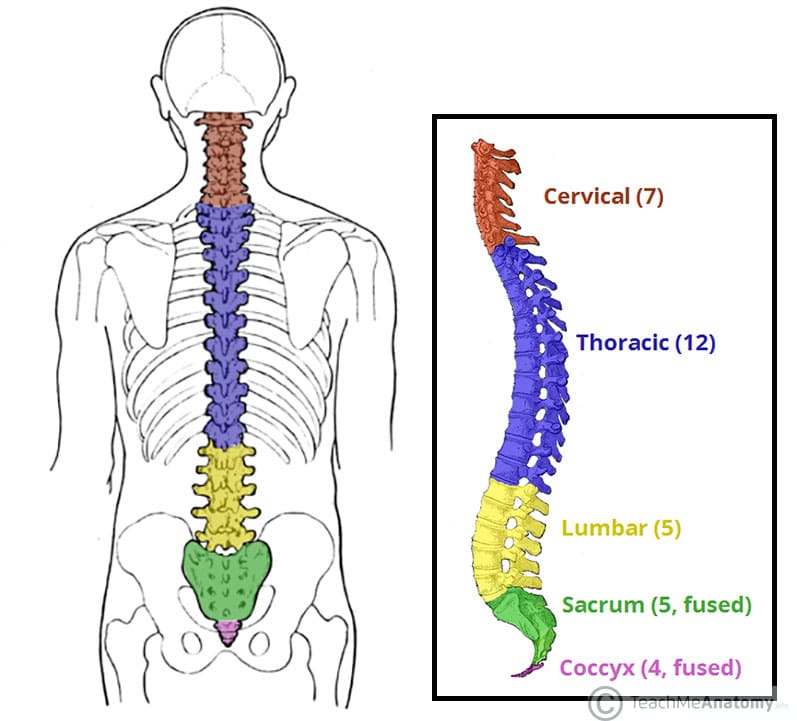

Here the spine is concave, curving toward the belly (lordotic). This area is very flexible and a common location of injuries. Vertebrae can be grouped into four groups: a. Injuries to the bones, ligaments or joints The spine connects to the hip bones at the sacro-iliac joints via a complex arrangement of ligaments.Strain of the large muscles of the back that hold the spine upright.Irritation of the smaller nerves of the spine that involve innervate or supply the discs between the vertebrae, facets and ligaments.Irritation of the large nerves as they exit the bony confines of the spine leading to the arms and legs.While many of us take the benefits of a healthy spine for granted, spinal pain is a sharp reminder of how much we depend on our back in daily life. The spinal column combines strong bones, unique joints, flexible ligaments and tendons, large muscles and highly sensitive nerves. Five bones in the lower back-the lumbar spine.

12 bones in the chest-the thoracic spine.Seven bones in the neck-the cervical spine.The remaining small bones or ossicles below the sacrum are also fused together and called the tailbone or coccyx. The spine is divided into four regions which contain vertebrae: the cervical, the thoracic, the lumbar, and the sacral.Hover over each part to see what they do. Vertebrae are numbered and named according to where they are located in the spinal cord. It is made up of several vertebral bodies usually fused together as one. Interactive Parts of the Spine & Vertebrae Sections. The bottom of the spine is called the sacrum. Sometimes a person may have an additional vertebra, which is called a transitional body and is usually found at the sixth level of the lumbar area (labeled L6). These vertebrae protect the brain stem and the spinal cord, support the skull and allow for a wide range of head movement. By the time a person becomes an adult most have only 24 vertebrae because some vertebrae at the bottom end of the spine fuse together during normal growth and development. The average person is born with 33 individual bones (the vertebrae) that interact and connect with each other through flexible joints called facets. The spine is composed of 33 bones, called vertebrae, divided into five sections: the cervical, thoracic, and lumbar spine sections, and the sacrum and coccyx. The spine supports about half the weight of the body. Structural support for the body, allowing us to stand upright.

It provides several important functions, including: The human spine is a complex anatomic structure that is the scaffolding for the entire body.